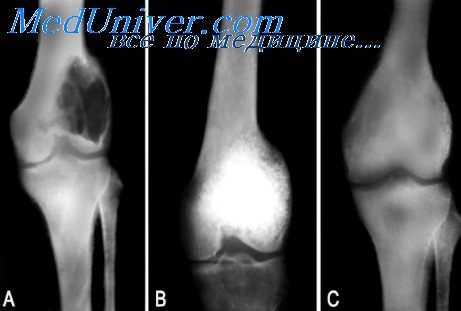

Для подтверждения диагноза выполняют рентгенографию позвоночника в двух проекциях. При компрессионных переломах более информативен боковой снимок, на котором обычно четко определяется уменьшение высоты передних отделов тел позвонков (передние отделы как будто «сплющены»). В сомнительных случаях пациентов направляют на КТ позвоночника. При наличии неврологических нарушений назначают консультацию невролога или нейрохирурга.

При оскольчатых переломах на снимках выявляется расширение тела позвонка и уменьшение близлежащих межпозвонковых пространств. Снижения высоты позвонка, как правило, не наблюдается. В сомнительных случаях для более подробного изучения состояния костных структур и мягких тканей больных направляют на КТ и МРТ позвоночника. Пациентам с оскольчатыми переломами назначают консультацию нейрохирурга, миелографию и электрофизиологические исследования (ЭМГ, ЭНГ), а также выполняют ликвородинамические пробы.